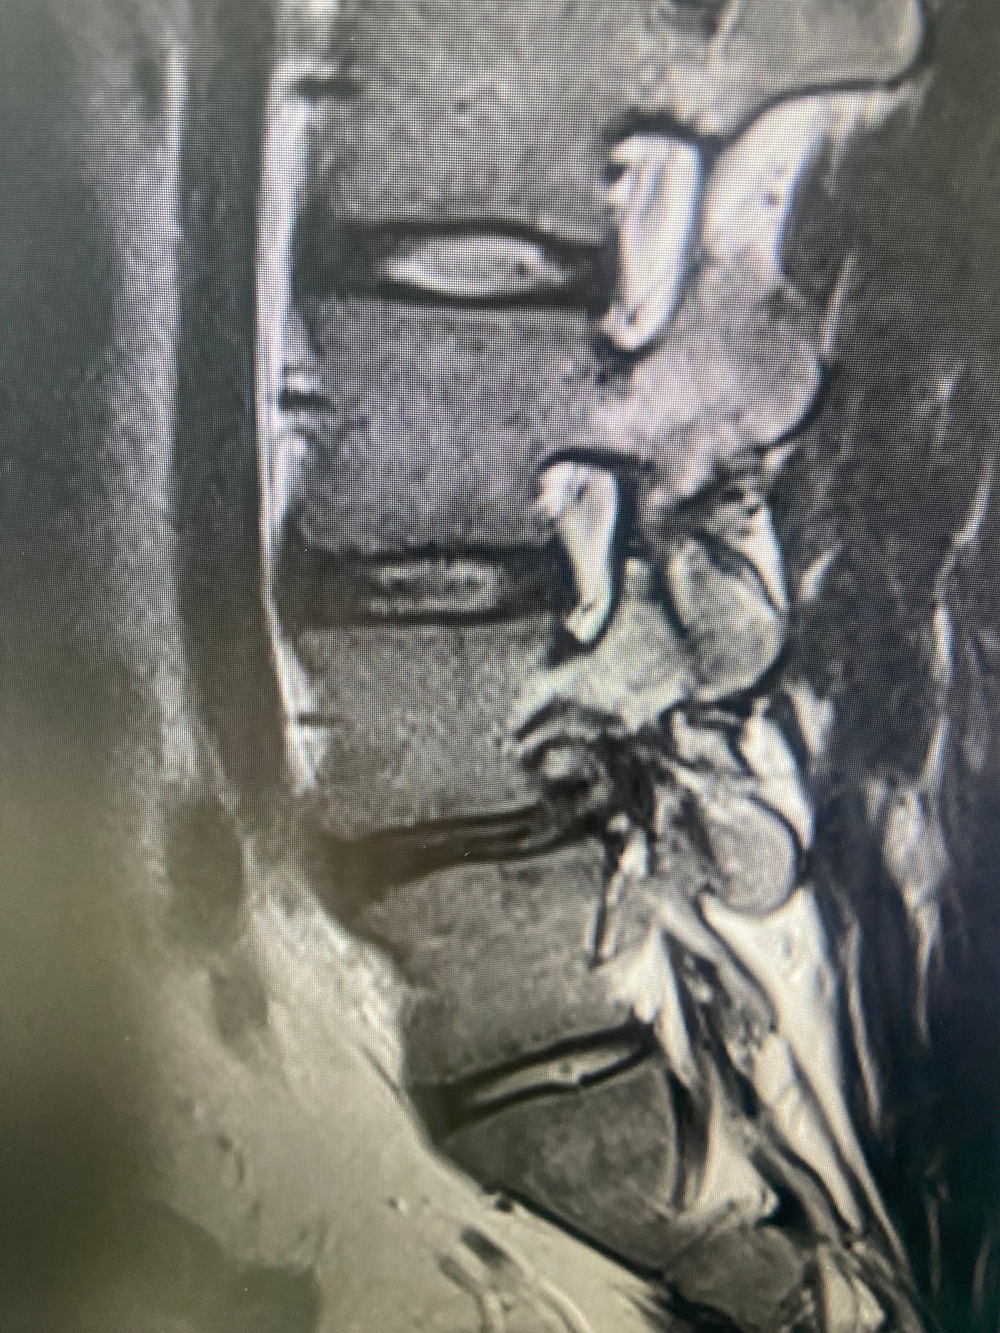

260408-N-TW242-1003 Okinawa, Japan (April 10, 2026) Lt. Cmdr. Ki Chang a Navy Medical Corps Officer and Staff Neurosurgeon at Naval Medical Center San Diego performed the first uniportal endoscopic spine surgery at U.S. Naval Hospital Okinawa, explains the procedure. (U.S. Navy photo by Courtesy Credit)